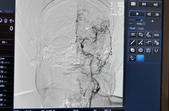

Капітальні ремонти провели в відділеннях кардіології, неврології, реанімації, комп’ютерної томографії та інтервенційної радіології.

«Абсолютно все було перероблено, ціле крило. Було оформлено кабінет для комп'ютерного томографа. Тут можна тепер робити тривимірний рентген можна обслідувати пацієнтам майже всі можливі частини тіла, з контрастом та без. Краще швидше діагностувати інсульт, тромбоемболію, також пневмонію, якщо є сумніви, онкологію», - розповідає завідувач відділення променевої діагностики Богдан Козів.